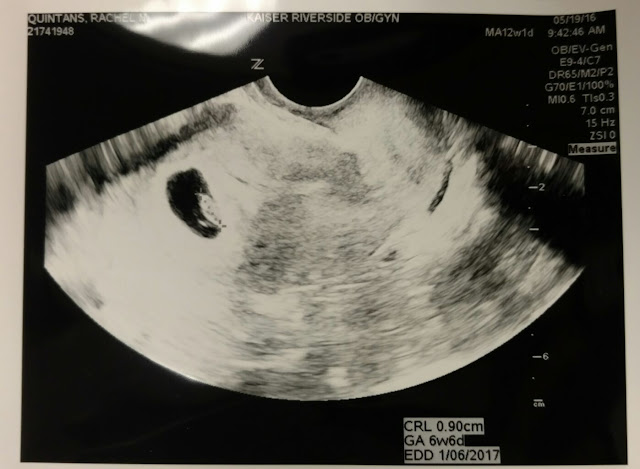

Our expected due date is January 5th, which marks us at 17 weeks. (Yes, that sonogram is from 6 weeks. It’s old.)